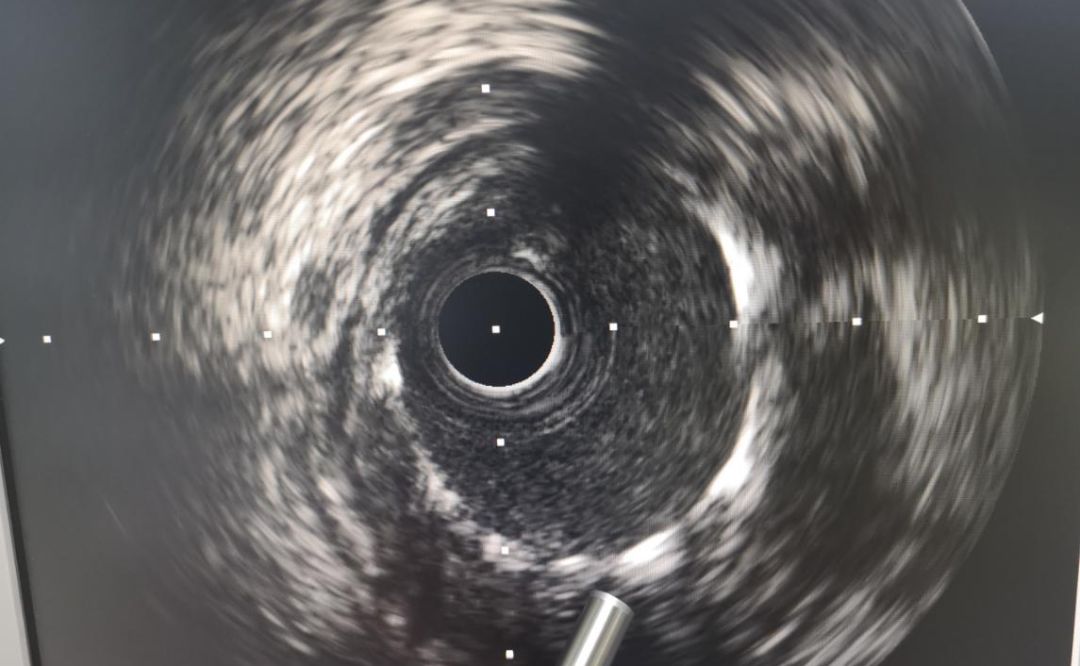

手术中,心血管病介入团队将患者的血栓抽出,植入支架,再经心血管内超声(IVUS)检查显示:患者支架贴壁良好,无夹层、血肿、血栓影,前向血流TIMI3级。经过45分钟,手术顺利完成,患者胸痛、胸闷症状消失,安全返回病房,患者及家属均对这次手术给予了肯定。

血管超声检查支架贴壁情况